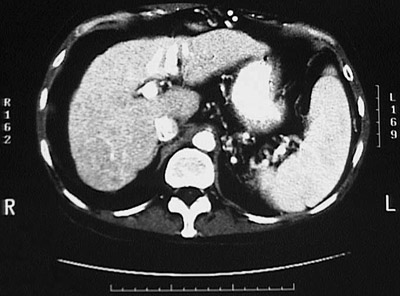

| CT scan of a normal liver. |